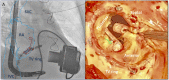

Tricuspid regurgitation in patients with left ventricular assist device (LVAD) has a significant impact on prognosis and quality of life, and its effects on liver and renal function could negatively impact planned heart transplantation. The aim of the present case is to report the feasibility and the clinical impact of tricuspid transcatheter edge-to-edge repair in LVAD patients as adjunctive bridge to transplantation strategy. A 59-year-old female patient previously treated with LVAD implantation (HeartMate III) and tricuspid valve repair with 32 mm rigid ring (Medtronic Contour 3D) as bridge to transplantation developed recurrence of significant tricuspid regurgitation with right ventricular decompensation needing inotropic support. Preoperative echo showed torrential tricuspid valve regurgitation Effective regurgitant orifice area(EROA 1.4 cm2 ) with suspicious of partial detachment of the prosthetic ring. The patient was successfully treated with transcatheter edge-to-edge repair with the MitraClip XTR device. Tricuspid regurgitation was reduced by 50% (postoperative EROA 0.7 cm2 ). She remained stable under continuous inotropic support with no other episodes of right ventricular decompensation and was successfully transplanted 30 days after the clipping procedure. Transcatheter treatment of tricuspid regurgitation in a patient with LVAD was an effective strategy to gain time and bridge the patient to heart transplantation.